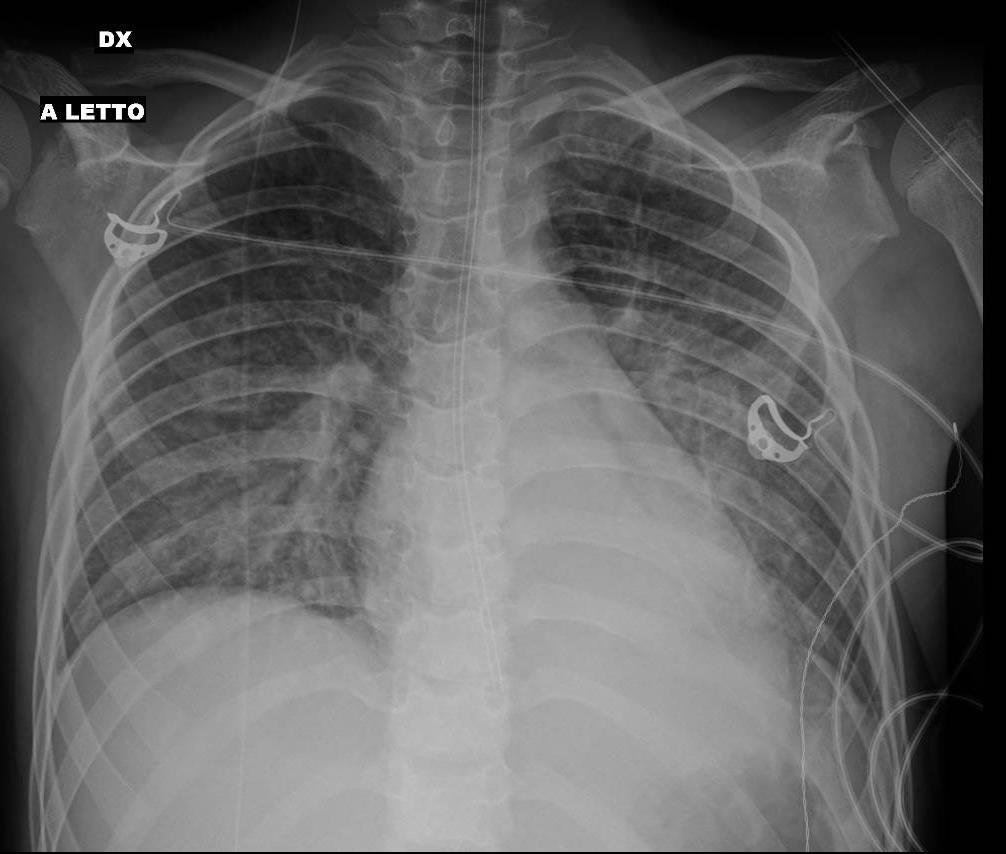

Pediatric COVID-19: MIS-C

Thoracic abnormalities

Cardiovascular abnormalities

Cardiomegaly

CHF or cardiogenic edema

Pulmonary parenchymal abnormalities

Lower lobe atelectasis

Bilateral opacities( ARDS)

Consolidation

Pleural abnormalities

Small pleural effusion

Mediastinal and hilar lymphadenopathy